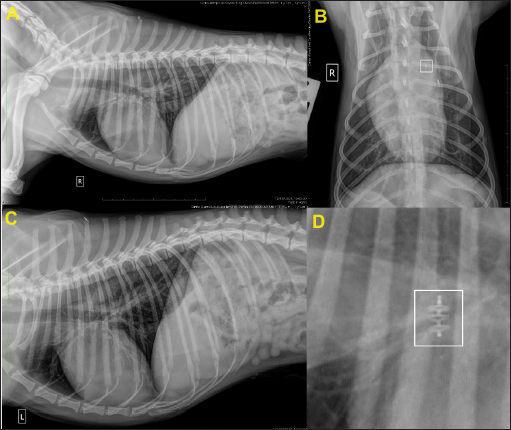

The duration of the entire surgery was 40 minutes, with fluoroscopic exposure times of 3 minutes 40 seconds. Recovery from anesthesia was uneventful, and the dog was able to walk and eat 3 hours later. Thoracic radiographs after 24 hours showed correct positioning of the device (Fig. 7).

Fig. 7. Thoracic radiographs obtained 24 hours after surgery. (A) Right lateral, (B) dorso-ventral, (C) left lateral views, and (D) close-up view of the device in the right lateral view (white square). In (B), note the thickness of the device (white square) compared to that of the identification microchip. Post-operative films show that the device is positioned correctly.